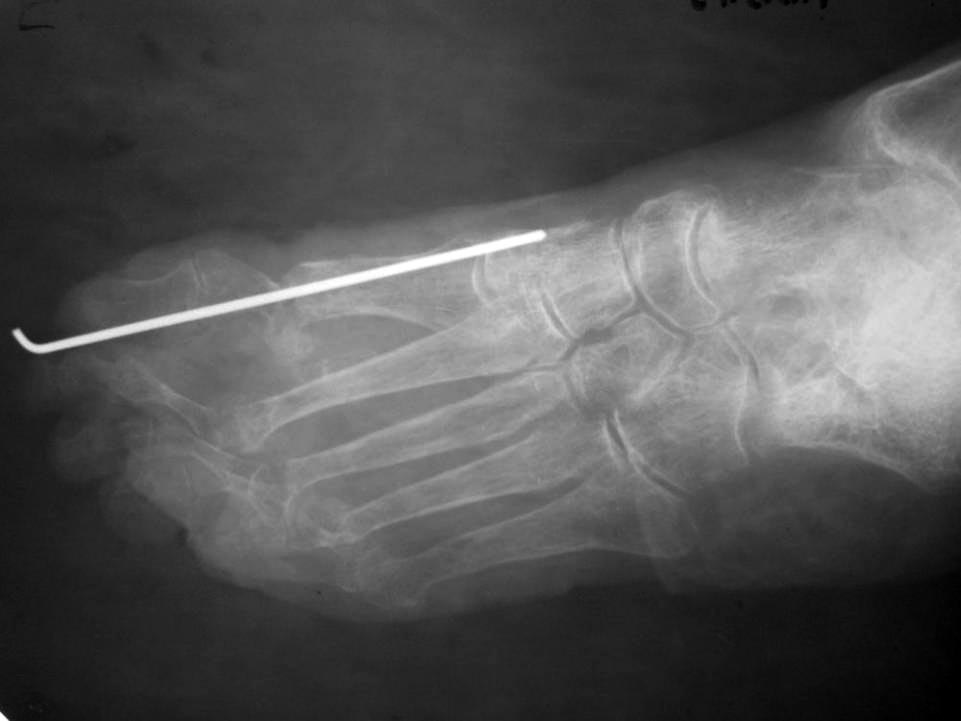

Обратилась больная 75 лет с нallux abductovalgus. начало деформации отмечает с 16 лет. лечение не проводилось.

причина обращения - появление болезненных, длительно незаживающих пролежней на подошвенной поверхности головок 1-х плюсневых костей. Уважаемые коллеги,подскажите пожалуйста план реконструктивной операции.

Случай очень сложный. И по рентгенограмме в одной проекции разобраться невозможно. Как минимум нужна еще одна проекция и фото стопы с тыльной и подошвенной стороны. Ведь по одному снимку неясно, какие пальцы лежат сверху, какие снизу, в каком состоянии сейчас пролежни. А еще лучше - компьютерная томограмма, которая позволит точно понять взаимоотношения фаланг и плюсневых костей, размеры, форму и положение сесамовидных костей.

рентген

Пациентке выполнен артродез 1-ого плюснефалангового сустава, резекции говок 2-3 плюсневых костей, субкапитальная остеотомия 4 плюсневой кости, тенотомиии разгибаталей 2-5 п. стопы. Раны зажили первичным натяжением.